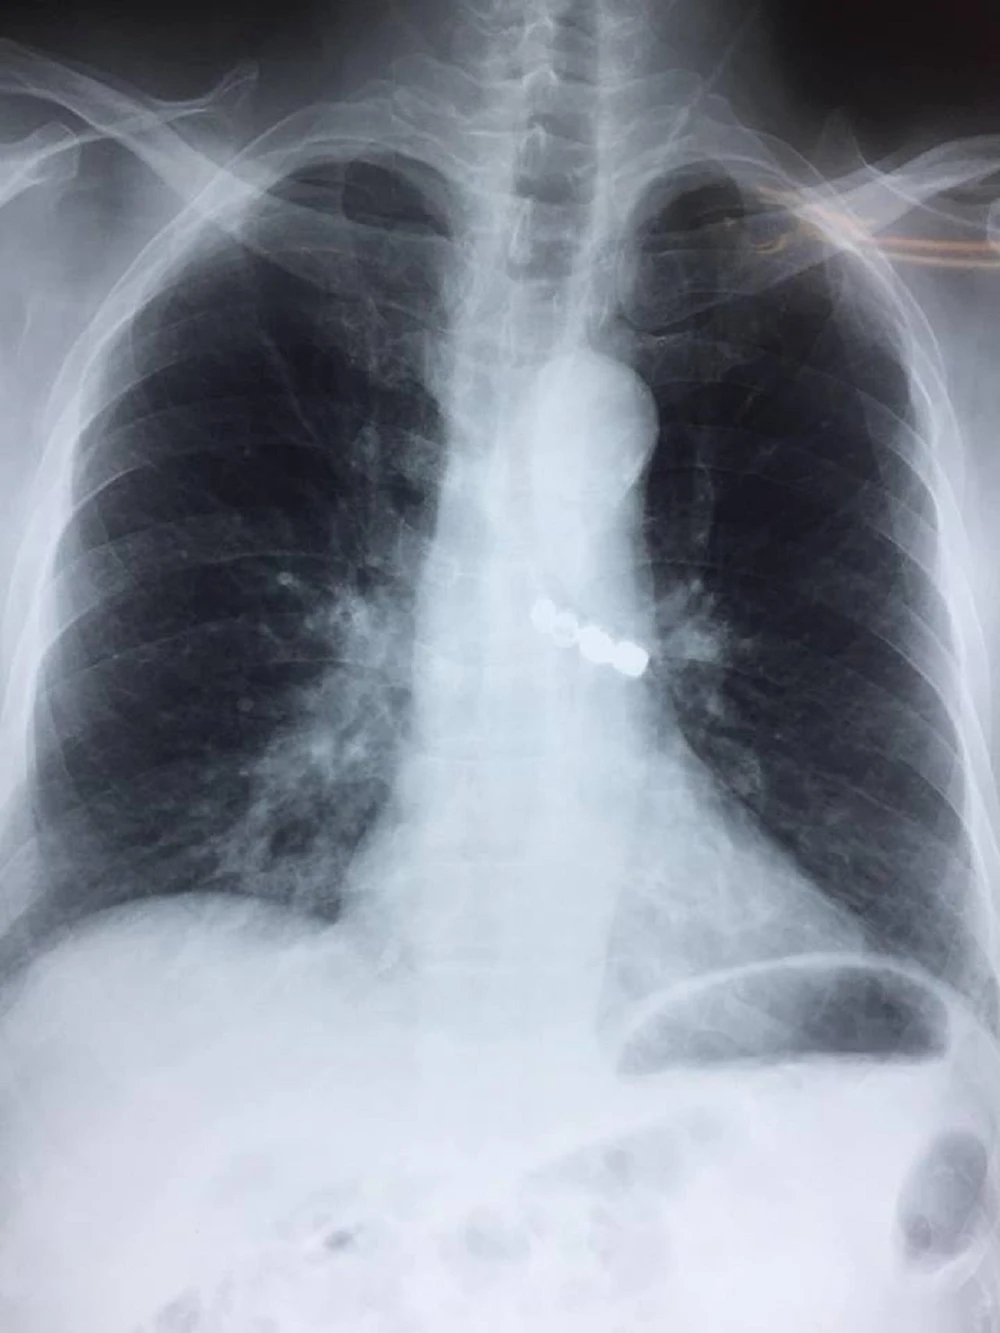

Theo gia đình kể lại, ông cụ đi làm răng giả, bị rơi răng giả vào bụng. Tại BV đa khoa tỉnh Thái Bình, bệnh nhân đã được nội soi dạ dày nhưng không thấy dị vật. Sau khi được chụp phim X-quang phổi thì phát hiện ra dị vật trong đường thở. Bệnh nhân sau đó được chuyển cấp cứu lên BV Phổi Trung ương.

Người bệnh đã nhanh chóng được gắp thành công dị vật ra khỏi phế quản, giải phóng đường thở. Dị vật là một cầu răng sứ bốn răng hàm dài 3,5 cm.